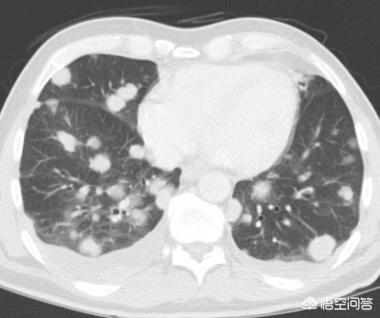

所谓肺小结节,是指直径小于1cm的肺结节,肺结节的大小和肺癌的可能性是正相关的。此回答,我们讨论小结节。

1、有的肺小结节,一开始就是肺癌。

肺癌分腺癌,鳞癌,大细胞癌,小细胞癌,类癌等等。这些癌在较小的时候,表现的不如大的时候那么典型。

2、有的肺小结节,一开始不是癌,而是不典型腺瘤样增生等,慢慢演变成浸润腺癌,这种多见于磨玻璃结节。

3、有的肺小结节,是良性的,不会演变成肺癌。

比如,肺内淋巴结,可表现为肺内小结节,甚至可以慢慢长大,但这个是良性的,不会恶变。有的磨玻璃结节,随访复查后消失,说明是炎症。还有的结节是结核,其他炎症,或者良性的肿瘤。

当发现了肺结节,要根据临床情况,CT表现等等综合分析,越小的结节,越难以定性,因此有时候才需要随访观察。